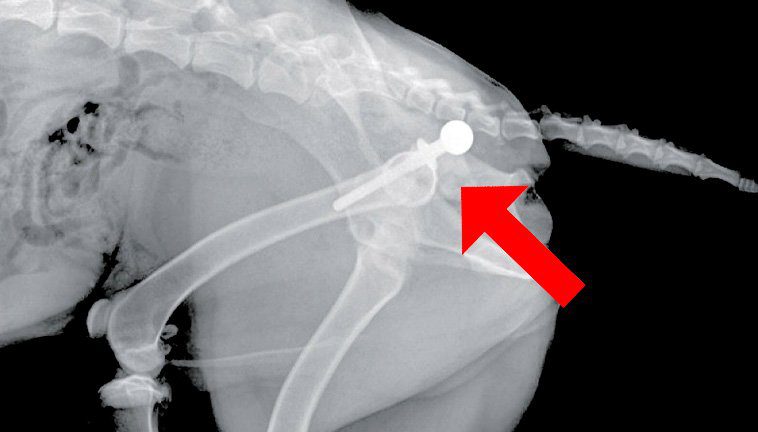

El diagnóstico se hará por historia, signos clínicos, examen físico general y radiografías, siendo esta última una prueba esencial y determinante. Para conseguir un buen diagnóstico es necesario sedar al animal. Según la gravedad de la displasia se distinguen diferentes grados: leve, moderada o grave.

A parte del mayor o menor grado de incongruencia de los fémures en los acetábulos, vamos a encontrar otras lesiones en la zona como degeneración articular u osteoartrosis (aumento de la radio opacidad), osteofitos o línea de Morgan. Todos secundarios a la patología.

Se realizan intervenciones como la osteotomía pélvica triple (otp), la artroplastia femoral, prótesis o sinfisiodesis púbica. En la otp o triple osteotomía pélvica se considera un tratamiento quirúrgico prematuro para evitar la aparición de osteoartrosis. Es una cirugía con alto nivel de dificultad. Las complicaciones pueden ser de leves a graves.

Por su parte, la artroplastia de la cabeza y el cuello del fémur consiste en seccionar la cabeza del fémur, lo que se recomienda en razas más pequeñas que para los demás métodos quirúrgicos. Por último, el reemplazo total de cadera implica extirpar esta articulación y sustituirla por una artificial. Es una cirugía menos accesible.

La prótesis consiste en poner material de acero o titanio tras cortar la cabeza femoral para que el mismo realice la función de cabeza. En España no se realiza de manera rutinaria por su alto presupuesto. En otros países sí está más desarrollado.